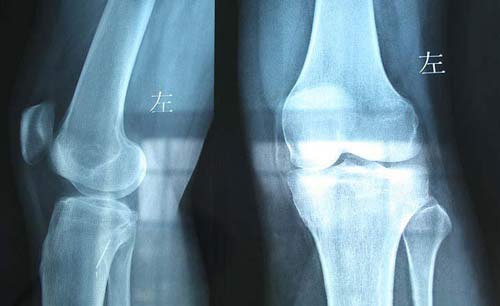

(图:患者治疗后双膝关节骨质恢复正常)

治疗3个疗程后,关节疼痛肿胀现象 消失,未有任何不适,行动能力恢复,摆脱了轮椅的自己可自由下蹲,上下楼梯都没问题。

结合吴阿姨的治疗效果,主治医生又为她制定了个体运动,改善关节活动度以及耐力,吴阿姨治疗结束后感觉神清气爽。“已经很久没有这样舒适的感觉了”,吴阿姨自己笑称。一年后,我院医务随访人员对吴阿姨进行回访,结果显示吴阿姨身体健康,关节病症再未发作。